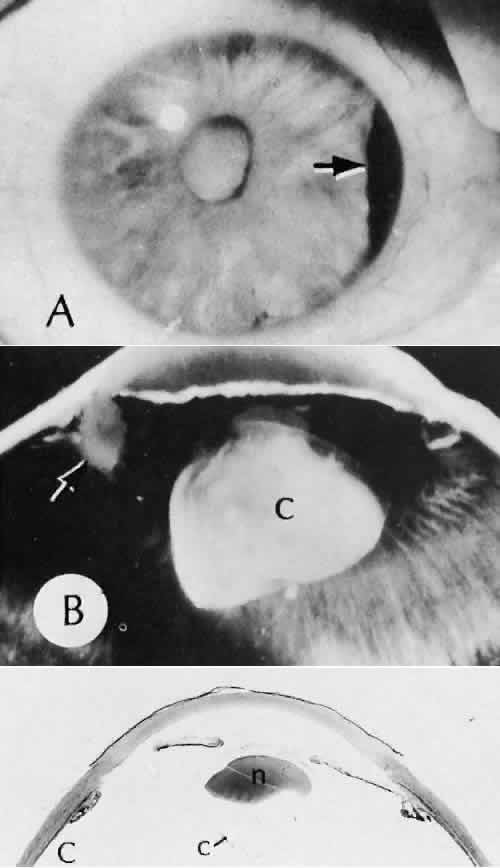

Descemet's membrane is only loosely adherent to the posterior stroma and may be stripped into the anterior chamber at the time of the corneal incision placement (Fig. 27) or injection of sodium hyaluronate. Splitting off of Descemet's membrane from the posterior cornea can lead to postoperative intractable corneal edema.89,90

Fig. 27. A case of stripping of Desce-met's membrane during a filteringprocedure (scleral cautery and iridectomy). A. The clinical appearance was one of extensive filtering bleb formation superiorly and regional dense corneal edema and opacification. B. The anterior chamber remains formed. Detached Descemet's membrane can be seen protruding into the anterior chamber. The patient died shortly after surgery from unrelated causes.C. The gross appearance of the area of detached Descemet's membrane extending into the anterior chamber.D. On the histologic section, the origin of detached Descemet's membraneextends to the region of the limbal wound. (Hematoxylin-eosin stain; × 16.) (Kozart DM, Eagle RC Jr: Stripping of Descemet's membrane after glaucoma surgery. Ophthalmic Surg 12:420–423, 1981.)